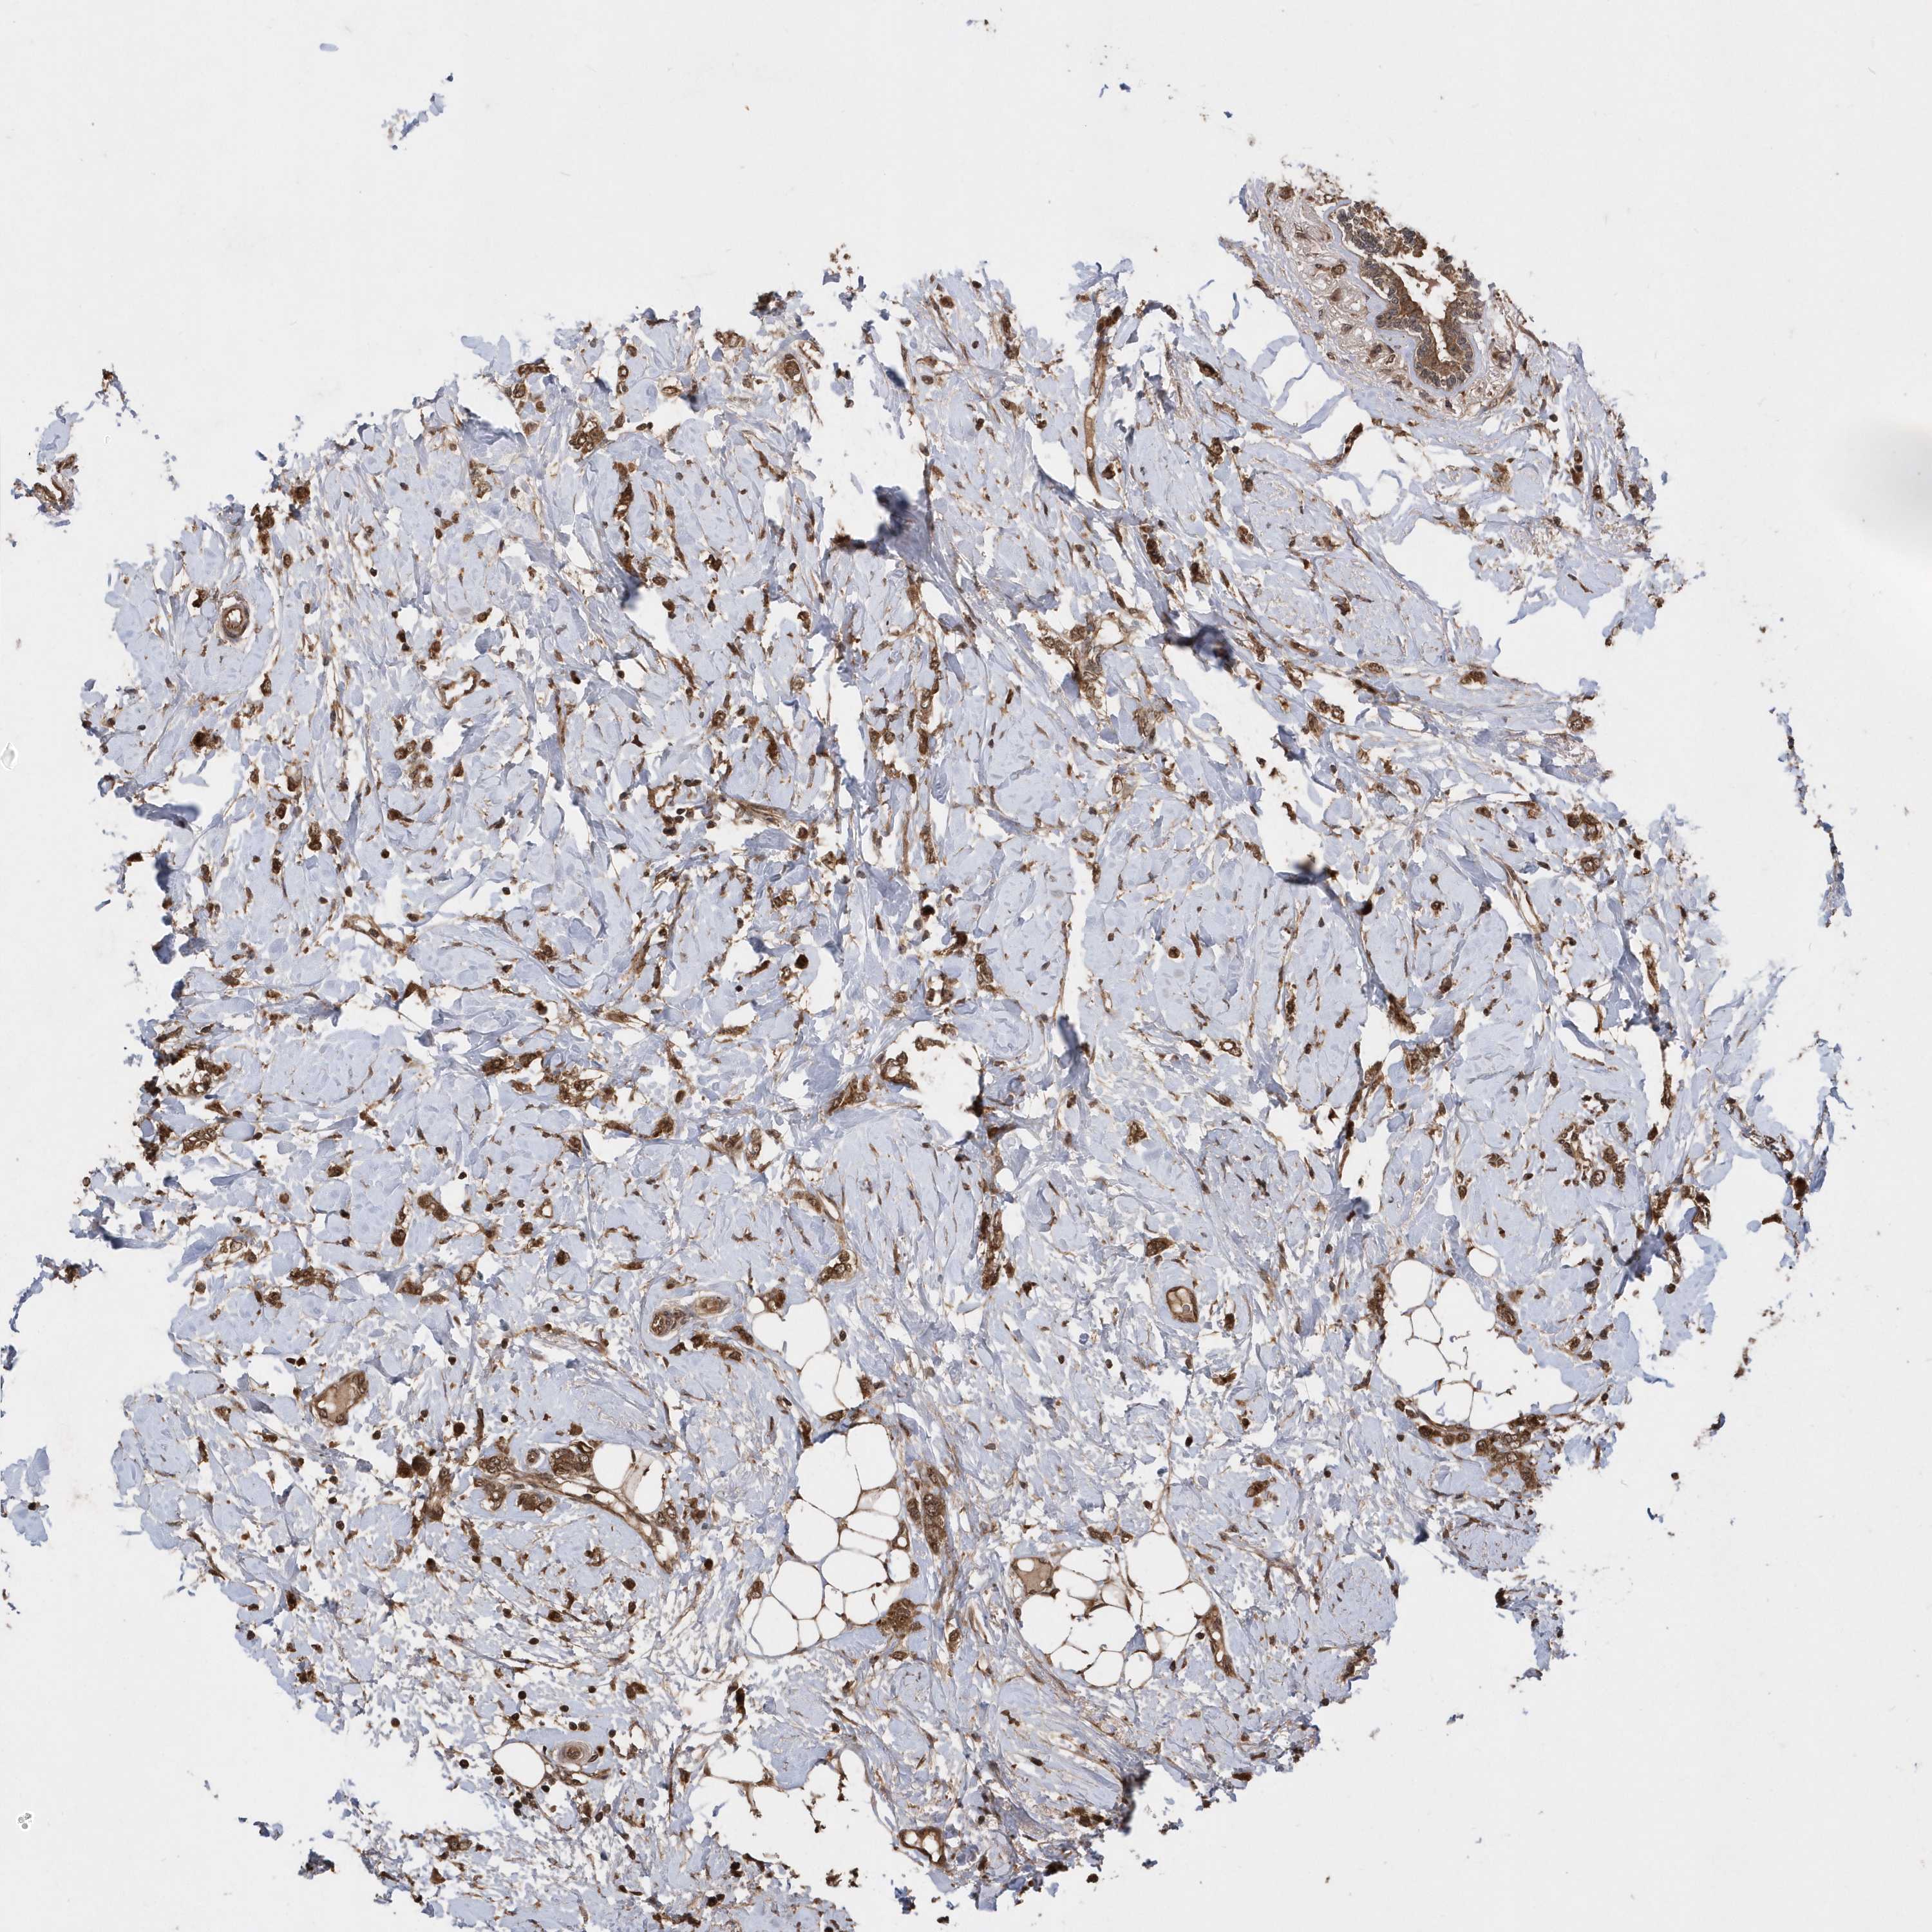

CANCER BREAST CANCER Show tissue menu

BRCA TCGA BRCA VALIDATION PROTEIN EXPRESSION

Breast cancer

Human cancer